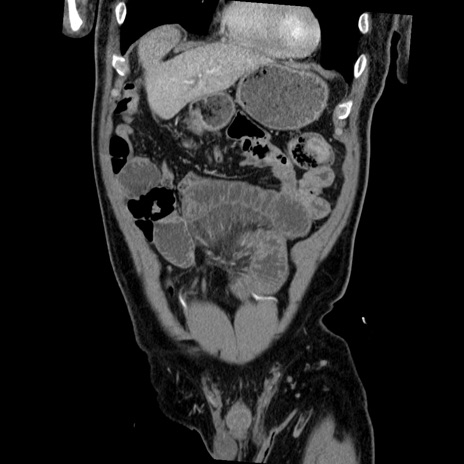

横断像

【症例】50歳代男性

【主訴】腹痛

【現病歴】AVMからの被殻出血のため回復期リハ病棟入院中。 本日午後3時頃急に下腹部痛が出現した。

【既往歴】AVM、被殻出血、虫垂炎、高血圧

【身体所見】意識晴明、左半身不全麻痺、会話の理解は良好、36.5°C、腹部:膨隆、全体に板状硬、下腹部正中に圧痛点あり、反跳痛-、筋性防御不明、右下腹部にope scar

【データ】WBC 9400、CRP 0.06